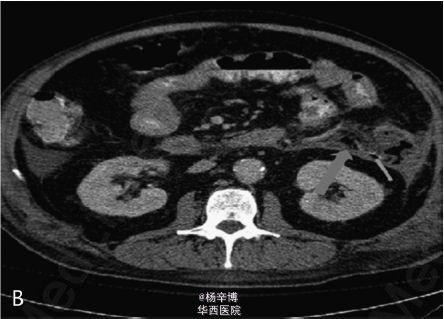

一59岁男性患者以严重腹痛、呕吐急性起病入急诊科,病史提示胆源性胰腺炎。体格检查:T 37.9℃,心率135次/分,呼吸32次/分,血压130/70mmHg,腹部肌紧张,广泛压痛及反跳痛。辅助检查:白细胞计数 24*10^9/L,血清淀粉酶 982IU/L,脂肪酶396IU/L,乳酸 2.2mmol/L,大便隐血阳性。遂诊断急性胰腺炎收入ICU。腹部CT示急性胰腺炎胰周广泛炎症,结肠旁沟游离积液,一钙化胆囊结石,未见胆管扩张或游离气体(图A)。患者症状逐渐加重,后行气管插管。即使给予了广谱抗生素,患者仍持续高热,在住院第11天复查CT示坏死性胰腺炎伴腹膜后近端结肠穿孔,可见肾旁前间隙渗出物及游离气体(图B)。讨论后行开腹探查术。术中见小肠和大网膜广泛粘连包裹降结肠左外侧壁。结肠穿孔位于结肠脾曲及近端降结肠。行粘连松解术及穿孔修补术后,予安置引流管及空肠造瘘,术后患者转入SICU。患者恢复较慢,手术2月后病情缓解出院随访。